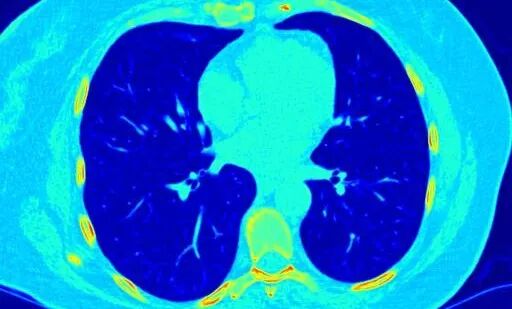

这两个项目需求的数据集都和我们曾经训练宠物识别器不一样。特别是医学上的CT影像。

△ 肺部的CT扫描

这种情况,还是用预训练过的权重更好,但是需要解锁所有网络层。然后我们在用新数据集,以正常的学习率训练。另外,斯坦福CS231n李飞飞主讲的王牌课程也论述了这个问题。